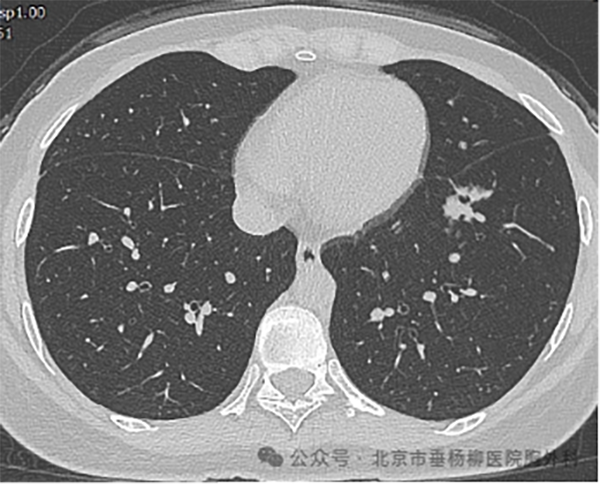

患者,女性,28岁,主因“发现左肺下叶结节3月。”来诊。查胸部增强CT:左肺下叶内前基底段部分实性病灶,长轴沿支气管走形方向,大小约4.1*1.1*2.0cm,边界清楚,周围伴磨玻璃影,边缘毛刺、分叶,其内可见空泡及支气管截断征象,周围可见血管伴行,增强扫描呈不均匀强化,恶性可能性大。考虑病人为青年患者,需慎重选择手术切除治疗及手术方式,有结节穿刺活检明确诊断指征。

术前CT

肺窗